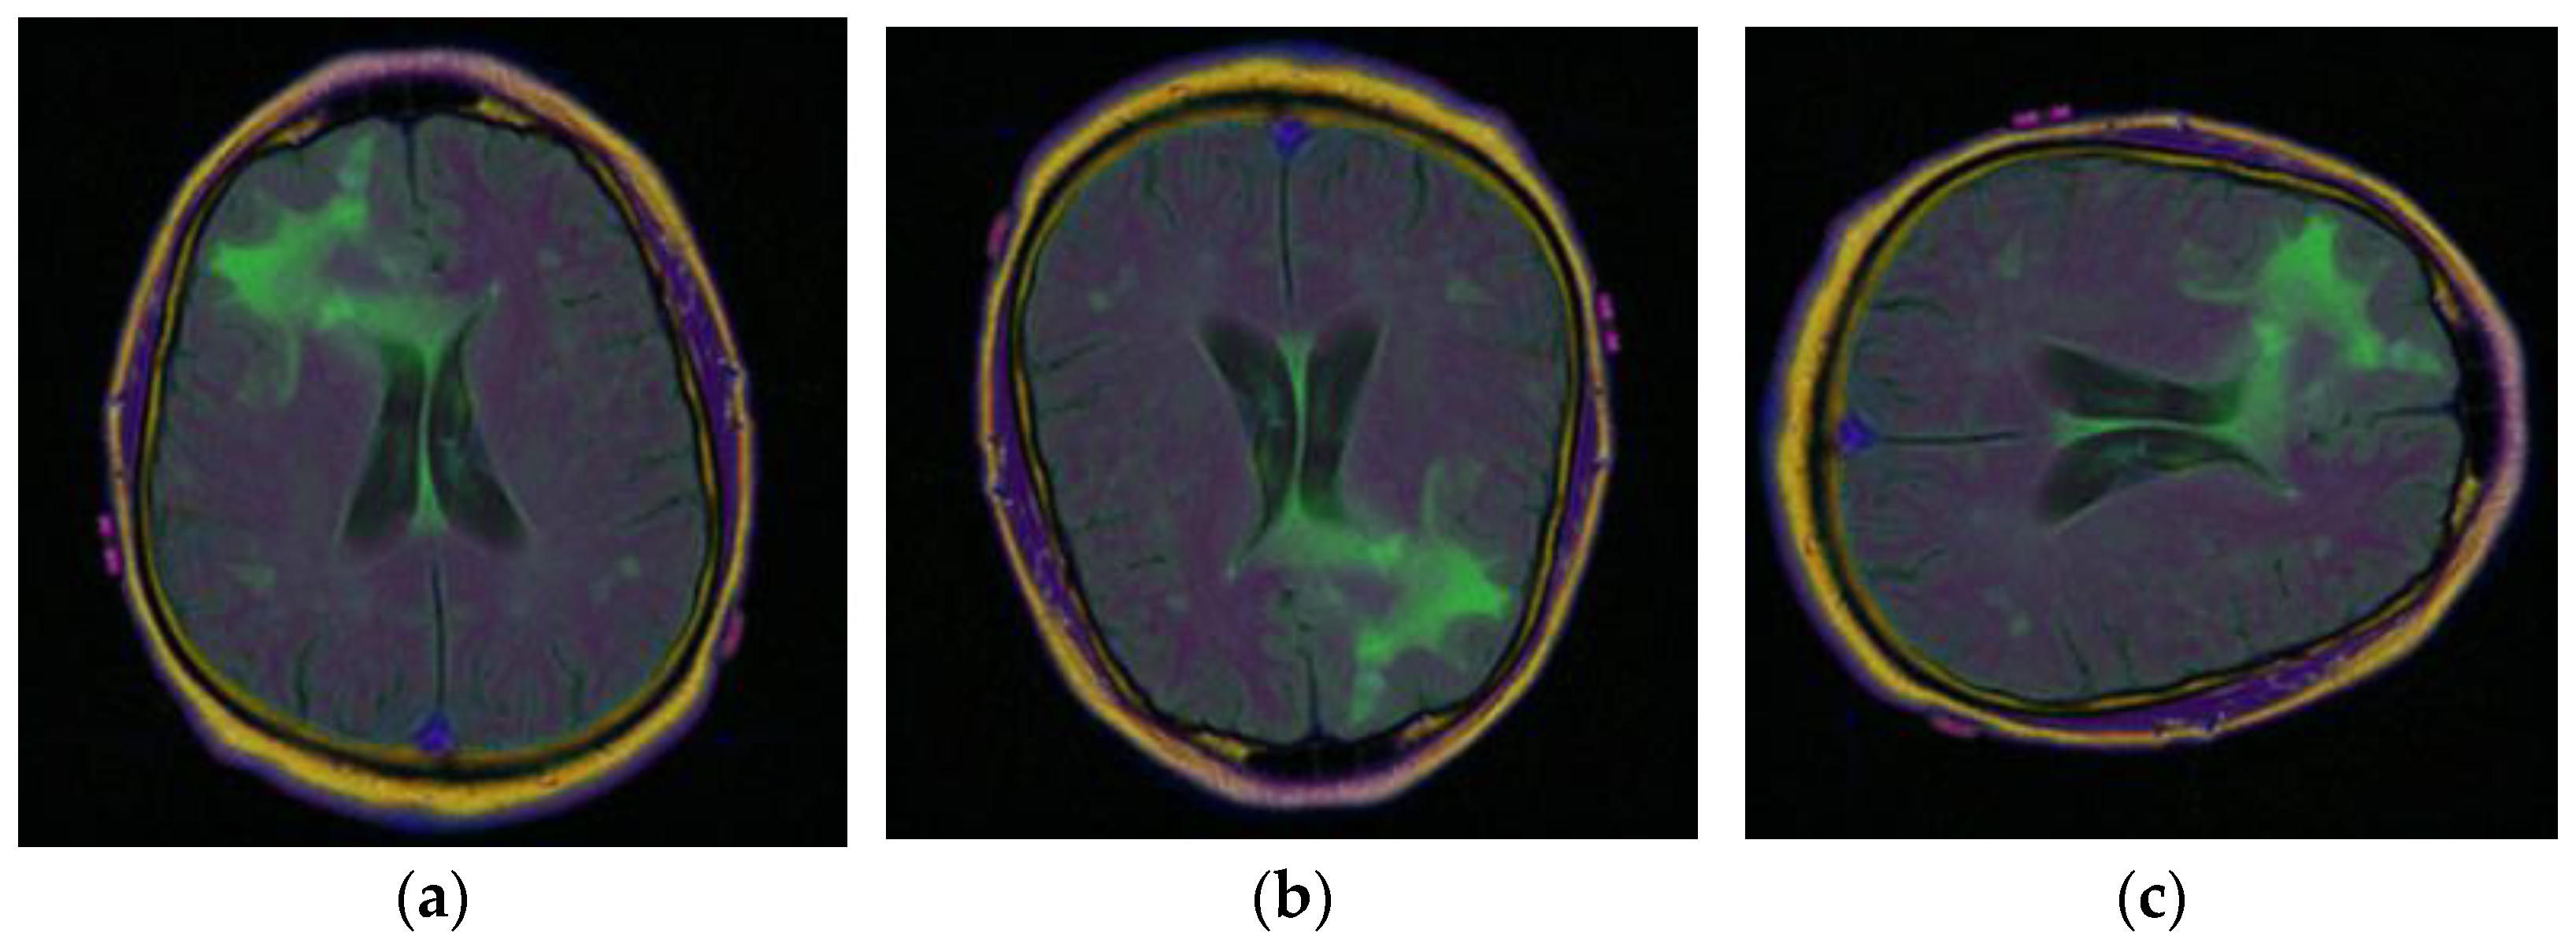

To obtain more, and more varied images of brain tumors, the data augmentation technique is used with the existing images. The different data augmentation techniques [31,32,33] that are applied are vertical flipping and horizontal flipping. Figure 6a displays the original sample of the brain tumor image, Figure 6b displays the vertically flipped image, and Figure 6c displays the horizontally flipped image.

Figure 6.

Samples of Brain MRI Images [31]: (a) Original Image, (b) Vertical Flip, (c) Horizontal Flip.